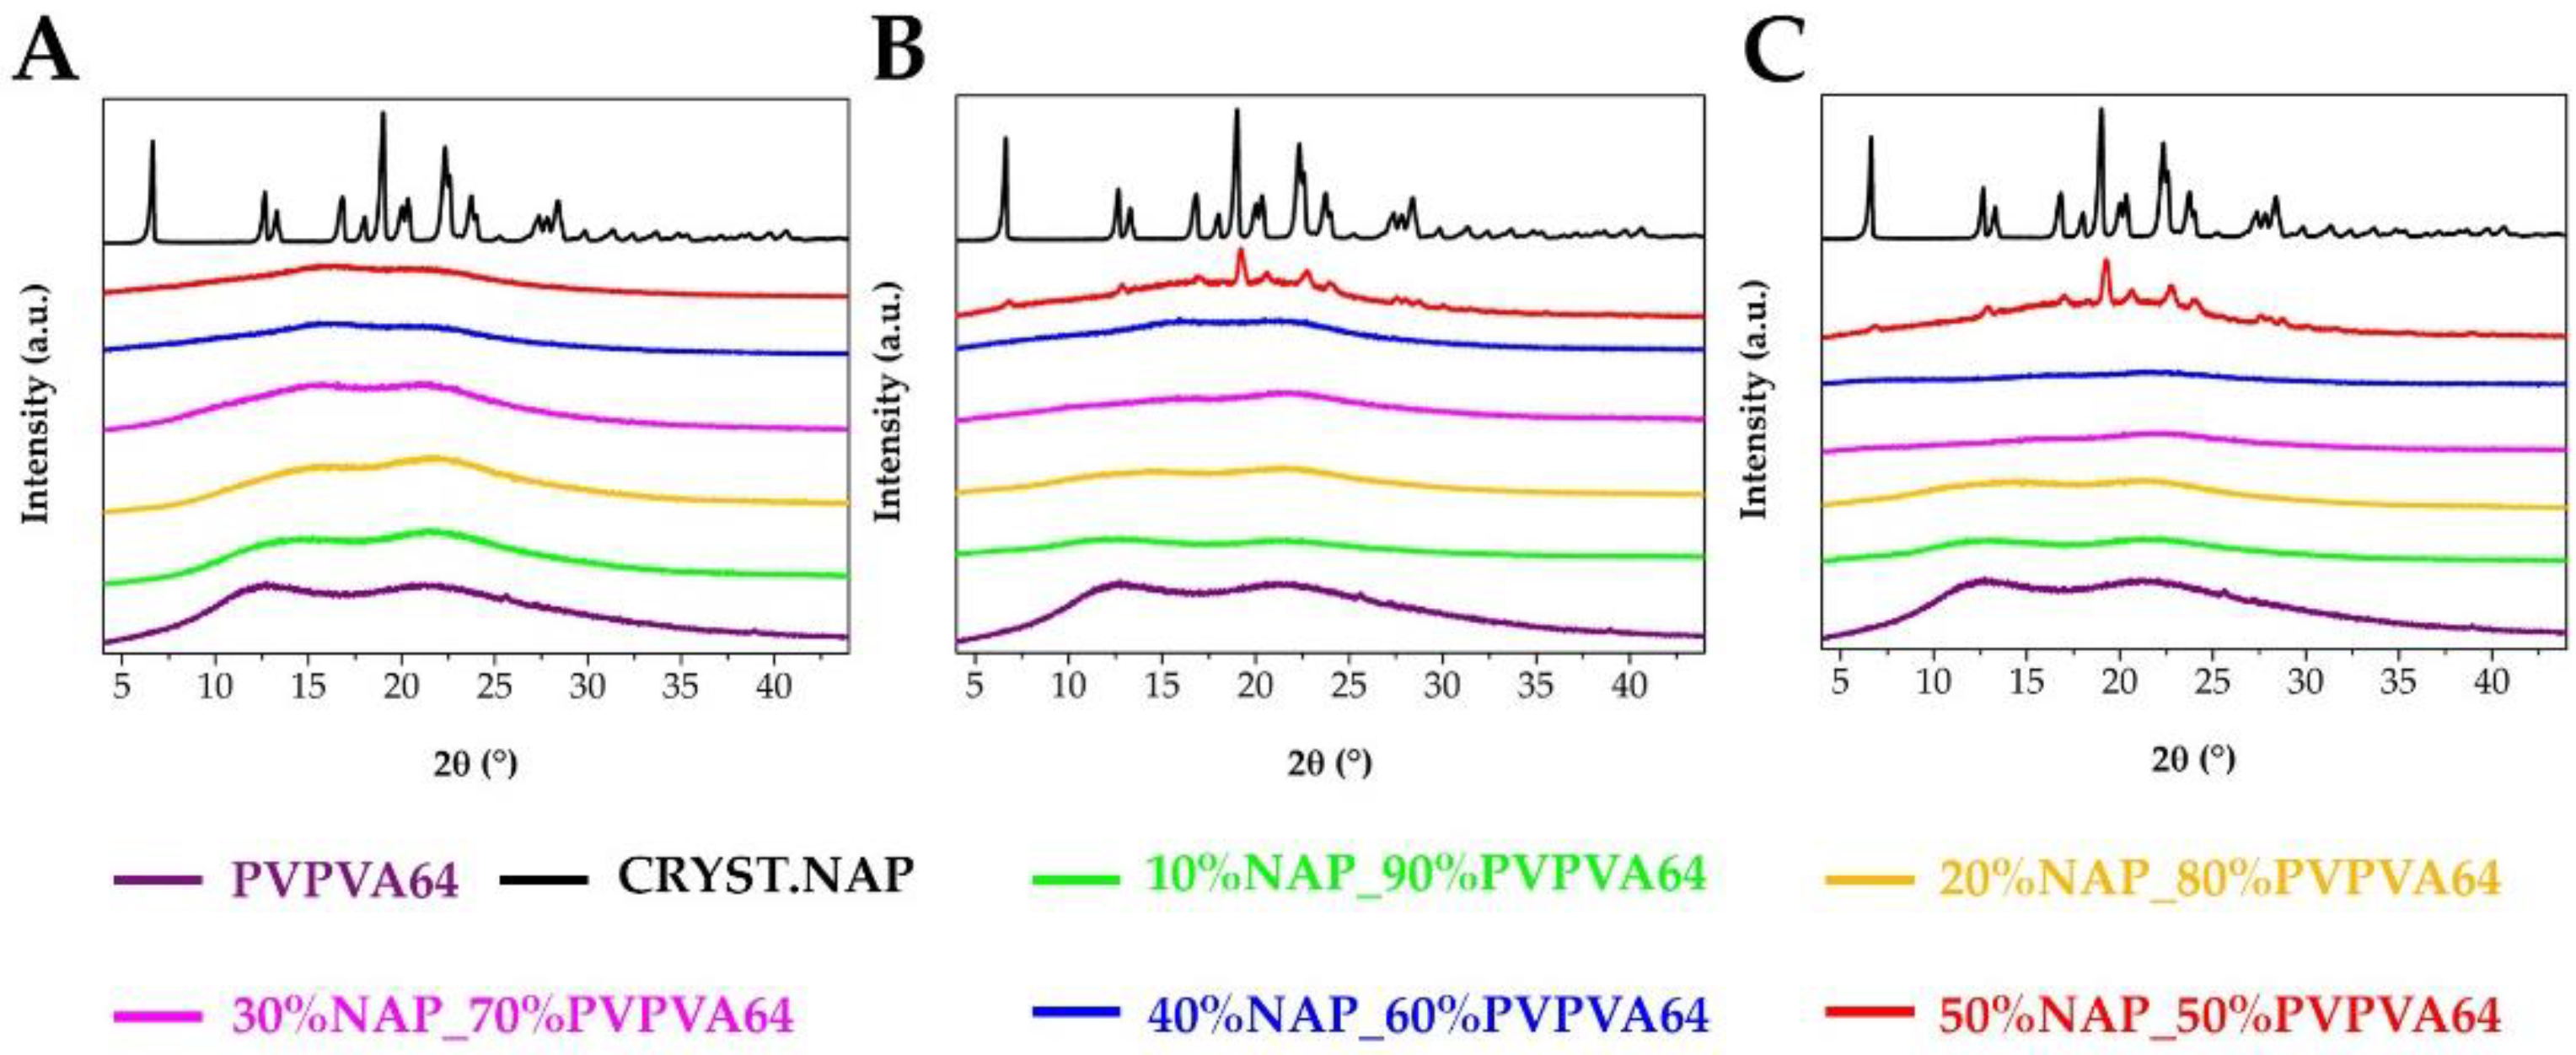

3.1. Preparation and Basic Characterization of the Samples

3.2. Measuring the Glass Transition Temperature with Different Methods

3.3. Effect of the Stress Stability Tests